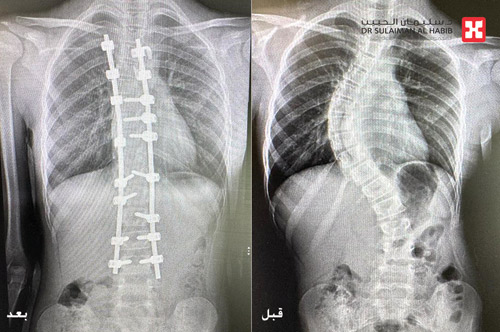

وقال د.السباعي إن المريضة قدمت إلى المستشفى وهي تشتكي من آلام حادة ومزمنة في الظهر، ناتجة عن انحناءين بالمنطقة العلوية والسفلية بالعمود الفقري، تسببا لها في حدوث ارتفاع بالكتف الأيمن أثناء المشي وتشوه بالشكل العام للجسم، بالإضافة إلى صعوبة الحركة وأداء المهام اليومية وممارسة حياتها بصورة طبيعية. وقد كشفت الفحوصات التي أجريت للمريضة إصابتها بحالة انحراف «جنف» مضاعف بالفقرات الصدرية والقطنية، وعدم القدرة على الانحناء على الأرض، وقد قرر الفريق الطبي إخضاعها لعملية جراحية، تم فيها تقويم العمود الفقري بنسبة 94 % وتثبيت ودمج الفقرات بجهاز مراقبة الأعصاب أثناء الجراحة « Nerve Conduction Monitoring and Somatosensory Evoked Potential» للتأكد من سلامتها والعمل الوظيفي لها، بالإضافة إلى جهاز الملاحة العصبية، الأمر الذي ساهم في إنجاح العملية.

وقال الدكتور واصف إن المريضة نُوّمت بالمستشفى لمدة 5 أيام، واستطاعت المشي خلال 24 ساعة فقط من العملية، مع استعادتها القدرة على السير بتوازن، فضلاً عن القوام والمظهر الطبيعي لاستواء طول الكتفين أثناء المشي، وأصبح بإمكانها الاستلقاء والنوم على ظهرها، وقد خرجت من المستشفى في اليوم الخامس وهي بصحة جيدة، كما تمت متابعتها في العيادة وفق جدول الزيارات ما بعد العملية، وتبين تحسنها وعودتها لممارسة حياتها بصورة طبيعية.